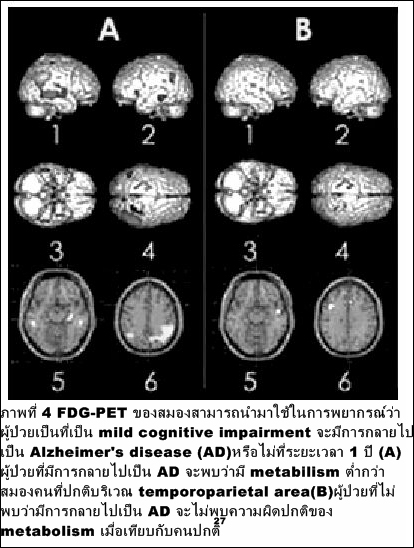

2. ความผิดปกติของสมอง อาทิ Alzhei-mer 's disease, Parkinson ' s disease, Epilepsy โดยจะช่วยตรวจหาโรคหรือพยากรณ์การเกิดโรคก่อนจะตรวจพบในทางคลินิก โดยเฉพาะใน mild cognitive impairment ที่อาจเปลี่ยนไปเป็น Alzheimer (ภาพที่ 4)